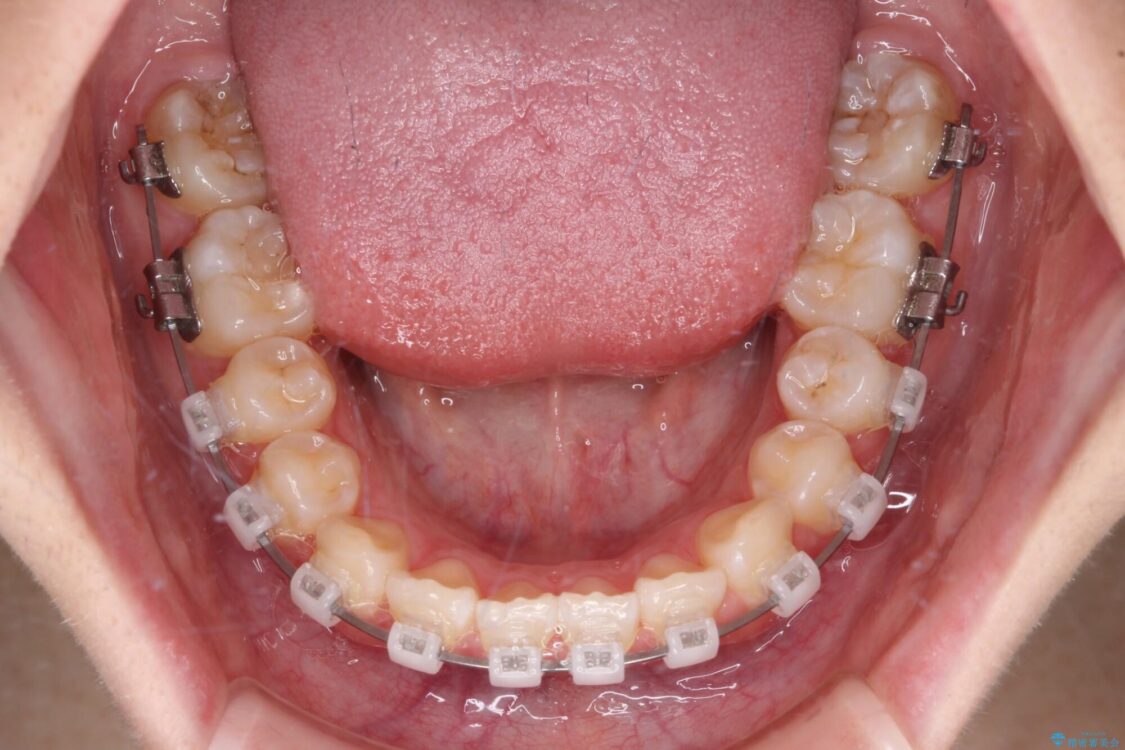

治療途中

• インビザラインは使える自信がない ワイヤー装置にて矯正治療 治療途中画像